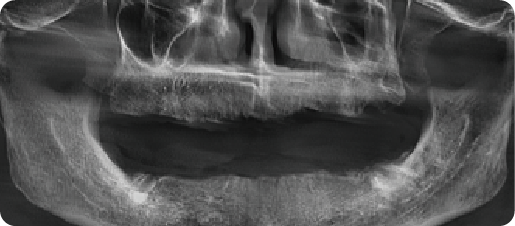

Half Arch Implant Dental Case

BEFORE

VS

AFTER

Name:Mrs YangAge:87

Evaluation: Abrasive cervical lesions with subsequent tooth fracture and mobility, attributed to long-term traumatic toothbrushing with a horizontal technique

Treatment Plan:Procedure: Extraction of compromised dentition and placement of four implants in the maxillary arch

Patient Feedback:l can finally eat anything I want without worrying. It's secure, doesn't harm my other teeth, and looks and feels so natural that I forget it's even there

To ensure the long-term durability of your implant restoration, I advise: • Meticulous oral hygiene. • Regular professional examinations and maintenance These are critical determinants of clinical success